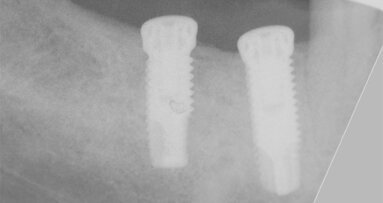

Nicméně, štěp je nutno zcela imobilizovat a zakrýt granulátem. Zpočátku jsem při horizontálních i vertikálních augmentacích používal nevstřebatelné, titanem vyztužené membrány. Tyto membrány fungovaly dobře, ale někdy bylo velmi náročné je umístit a mnozí lékaři je nepřijali dobře. Vyvstala otázka: Proč nepoužívat zbývající kostní stěnu chytřejším způsobem? Začal jsem tedy s dobrými výsledky používat při horizontálních augmentacích vstřebatelné tuhé membrány. Dnes používám přírodní kolagenní membránu Geistlich Bio-Gide.

Připevnili jsme s týmem kolagenní membránu titanovými piny ke kostním stěnám a vyplnili prostor pod membránou tak, aby vznikl velmi stabilní štěp. Celý štěp vypadá jako hodně naplněná klobáska (pozn. redakce: sausage – klobása anglicky). Materiál Geistlich Bio-Gide působí v prvních týdnech hojení jako imobilizovaná „nacpaná“ tkáň ve tvaru klobásky.

Dosahujeme s touto technikou použití směsi materiálu Geistlich Bio-Oss a autogenních kostních částic v poměru 1 : 1 velmi předvídatelných výsledků. Obvykle odebereme pomocí kostních škrabek dostatek kosti na štěp. Částice Geistlich Bio-Oss se do štěpu dobře začlení a pomáhají zmírnit resorpci štěpu. To bylo dobře prokázáno jak klinicky, tak histologicky v naší nedávné sérii prospektivních případů.1

Materiál Geistlich Bio-Gide má všechny tyto vlastnosti. Absenci titanové výztuže lze spolehlivě překonat upevněním membrány z lingvální nebo palatinální a vestibulární strany. Dnes již používáme membrány vyztužené titanem výhradně u vertikálních defektů.